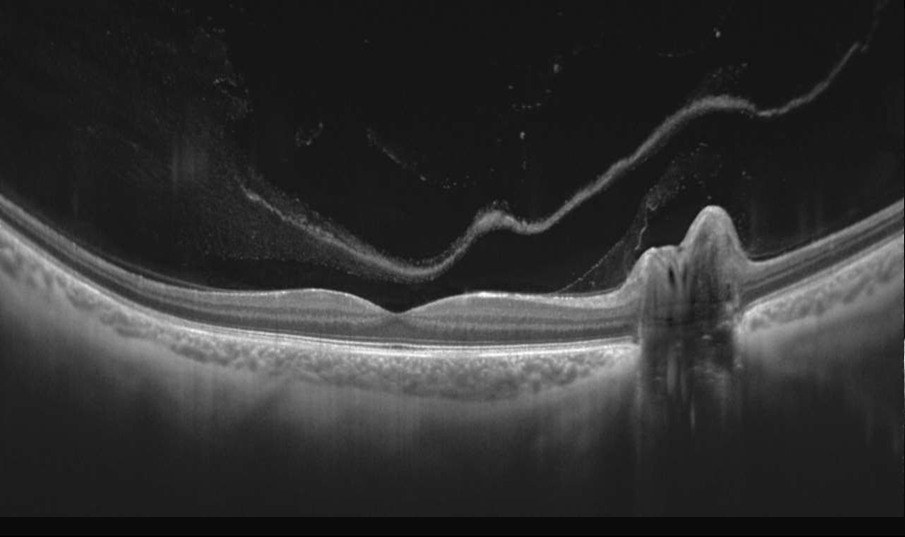

LE NOUVEAU LOGICIEL EXTENDED DEPTH ET LES CAPTURES FULL RANGE

Avec des scans présentant le nouveau logiciel Extended Depth, basé sur notre technologie Full Range, fournit des scans d'une profondeur accrue pour une observation fiable et pratique des cas difficiles. Avec des scans présentant une profondeur étendue, ce nouveau mode d'imagerie est parfait pour diagnostiquer même les patients très myopes.